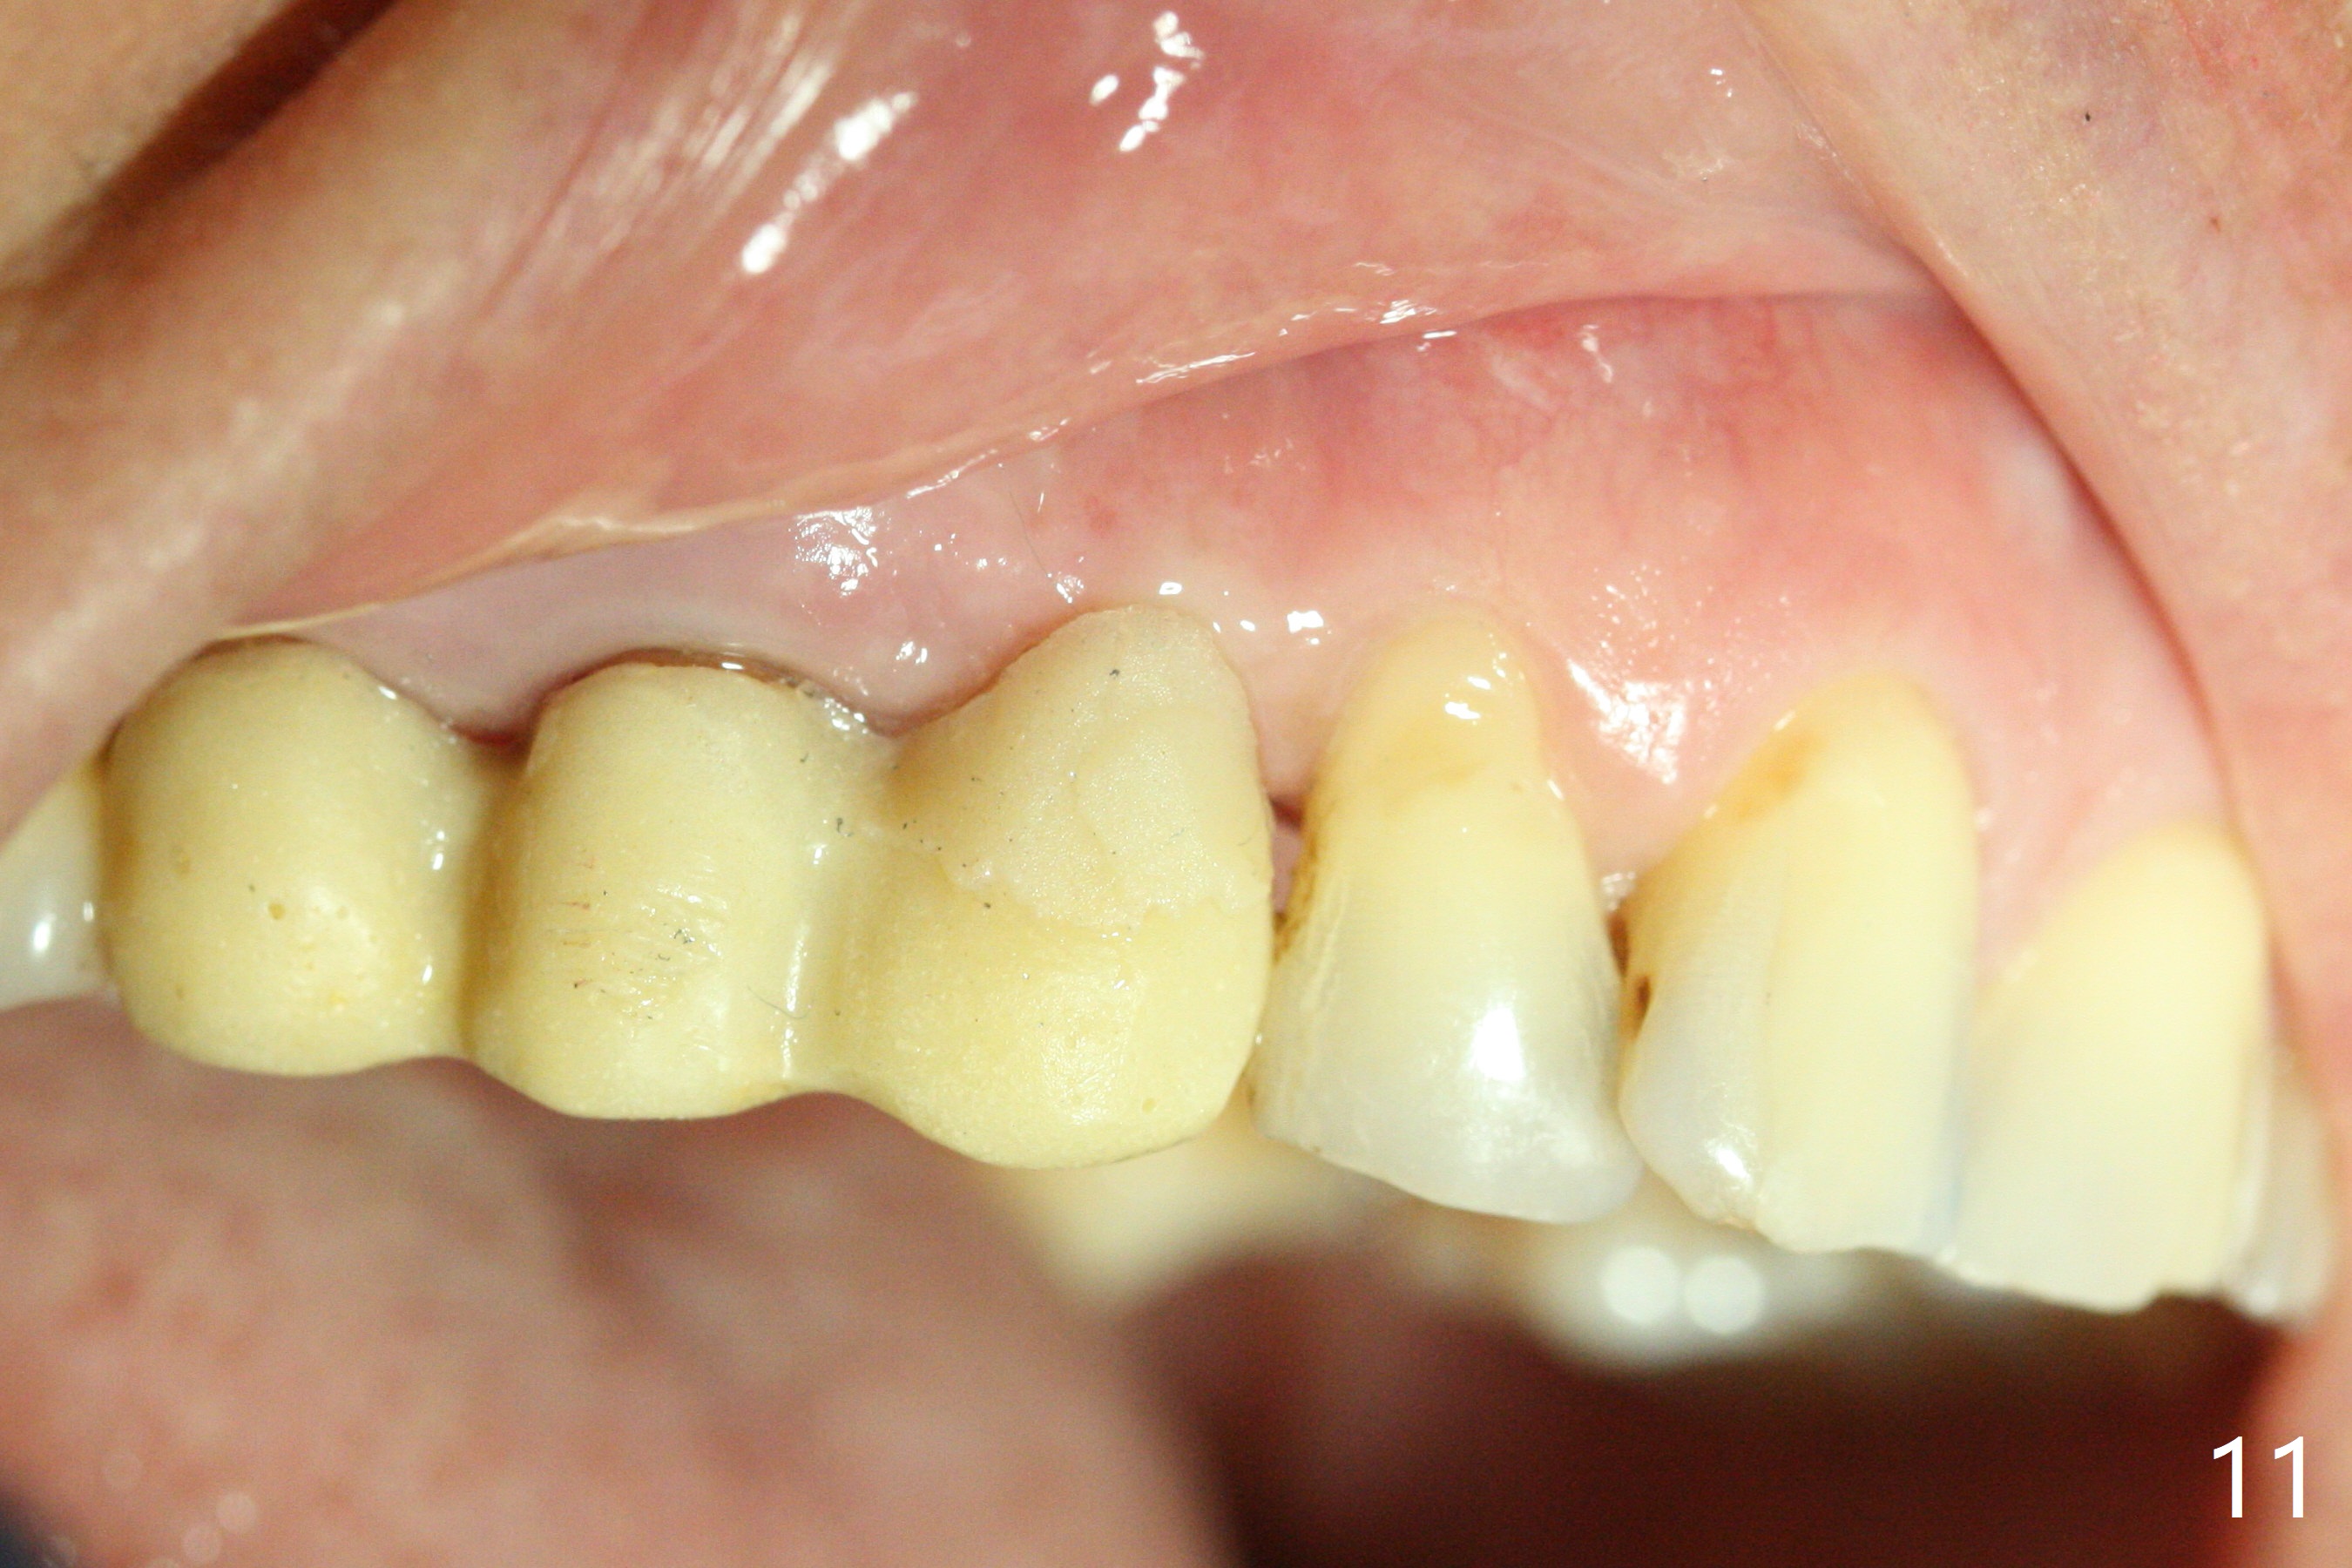

Osteotomy starts with guide and 2.2 mm drill for initial 3.5 mm palatal. A semilunar incision is made buccal to remove the impacted canine (#6 by sectioning). With direct vision buccal and palatal, the final osteotomy is finished free hand with 1.2 and 1.5 mm drills. Initially buccal perforation occurs, the osteotomy route is corrected later (Fig.1). When a 2.5x15 mm 1-piece implant is being placed, it perforates into the buccal concavity again. After redirection, the trajectory seems to be acceptable (Fig.2: CT coronal section). Three coronal implant threads are exposed partially palatal (Fig.3: CT 3-D palatal view). The implant is then turned 2-3 times with insertion torque reaching 40 Ncm. The incision is closed with suture following Osteogen plug placed in the most coronal portion of the socket (Fig.4 P) and allograft (*) in the remaining socket around the apical portion of the implant as well as palatal. The incision does not heal 1 month postop (Fig.5). PRF membrane will be placed next visit. Next visit the wound in fact is healing (Fig.6). PRF is unnecessary. The patient will return for impression 3 months postop. To be cosmetically pleasing, prepare local anesthetic and Laser for gingivectomy (Fig.7 red curved line). There is no bone loss around the implant 3.5 months postop (Fig.8). With topical, minor gingivectomy with laser creates papillae mesial and distal to the implant (Fig.9, 10 (incisal view)). After reline, there is appearance of a canine (Fig.11). The patient returns for impression 5 months postop; there is bone around the apex of the implant (Fig.12 *). The hard and soft tissues remain healthy when final restoration is delivered (Fig.13,14). The buccal plate reforms and #6 socket heals 12 months postop (6 months post cementation, Fig.15). The gingiva remains healthy at #4-6 nearly 2 years post cementation (Fig.16).